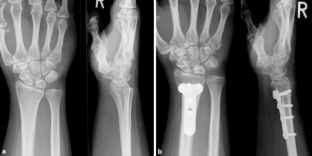

Abb. 3